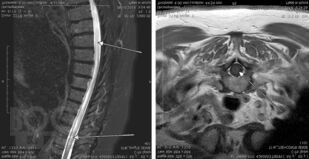

В руководстве представлены сведения о редко встречающихся (в том числе орфанных) неврологических синдромах и болезнях, сгруппированных в 4 главы в зависимости от этиологии: аутоиммунные и воспалительные; врожденные пороки развития нервной системы, наследственные и дисметаболические; опухоли нервной системы и паранеопластические синдромы; нейродегенеративные заболевания. В отношении каждой болезни представлены эпонимические сведения, шифр по МКБ-10, эпидемиология, этиология, патогенез, патоморфология, клиническая картина, диагностика, дифференциальная диагностика, лечение и прогноз. Все разделы книги иллюстрированы собственными клиническими случаями и результатами их обследований.